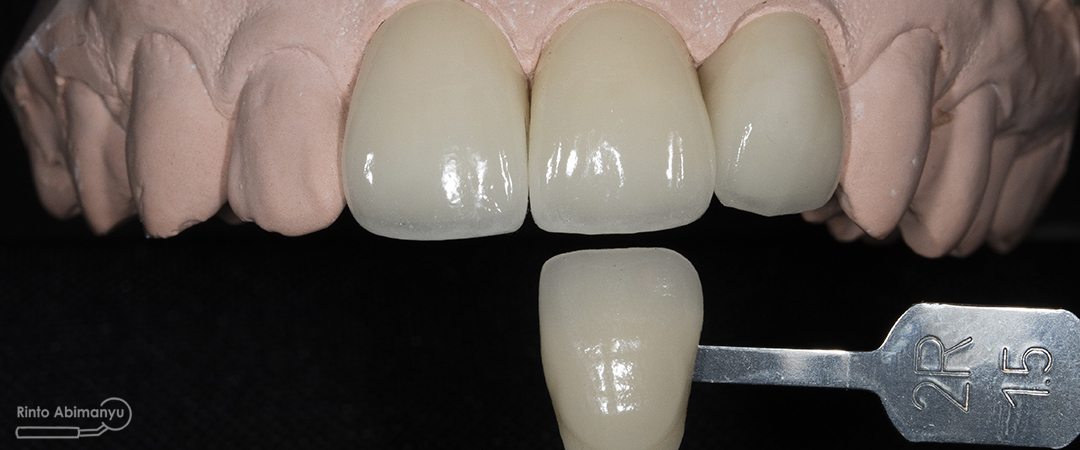

Crown dari lab sudah jadi dan ketika saya coba cocokkan dengan shade guide hasilnya sangat memuaskan… Baik warna dan bentuk sesuai ekspektasi…..

Shade crown sesuai dengan warna shade guide yang kita pilih